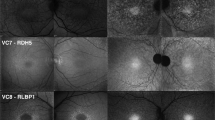

Multimodal imaging of the 16 cases with achromatopsia are provided in Figs 1, 2, and in the Supplementary Figure 1, and the main imaging features are summarized in Table 2. Complete multimodal imaging acquisition was obtained in the right eye for ten subjects, and in the left eye for six subjects. The eight control subjects selected for the semiquantitative NIR-AF and SW-AF plots did not differ from the 16 achromatopsia cases in terms of age (26.8 versus 25.1 years, P = 0.78) and gender (male:female ratio of 3:5 versus 5:11, P = 1.0).

Multimodal imaging in eight patients with achromatopsia displaying normal near-infrared autofluorescence features, and corresponding optical coherence tomography and short-wavelength autofluorescence images. Semiquantitative autofluorescence plots (right) show normalized autofluorescence signals, plotted after segmentation along semi-circles centered on the fovea. The horizontal dimension of the inner segment ellipsoid interruption on optical coherence tomography, if present, is reported as a striped area on autofluorescence plots. SD-OCT = spectral domain optical coherence tomography; SW-AF = short-wavelength autofluorescence; NIR-AF = near-infrared autofluorescence; yo = year old; M = male; F = female.

On SW-AF, the most frequent abnormal feature was a pathognomonic perifoveal hyperautofluorescent ring, that was observed in n = 12 subjects (75%). The semiquantitative autofluorescence plots contributed to identify this ring in a low-quality autofluorescence acquisition due to photophobia, nystagmus and poor fixation (Case #6, Fig. 1). The four cases without perifoveal hyperautofluorescent ring on SW-AF had an abnormal foveal SW-AF profile, consisting in an enlarged (Case #5, Supplementary Figure 1) or a steep central SW-AF depression (Cases #1, Fig. 1; #2 and #12, Fig. 2).

On NIR-AF, the usual increased autofluorescence was present at the center of the macula in all eyes, with a variable signal strength ranging from very faint (Case #9, #11, Fig. 2) to intense (Case #13, #14, Fig. 1; and #8, Fig. 2). Within the macular hyperautofluorescent area, the most frequent abnormal feature of NIR-AF was a central hypoautofluorescent spot of variable size, that was observed in n = 7 subjects (44%), all displayed in Fig. 1. This central hypoautofluorescence, visible on the NIR-AF images, was confirmed by the semiquantitative NIR-AF plots, where it appeared as a central depression whose lowest value reached below the values of the control curve. Among those subjects, two presented in addition a perifoveal NIR-AF hyperautofluorescent ring, colocalizing with the border of the hypoautofluorescent area, as demonstrated by the sharp demarcation visible on semiquantitative autofluorescence plots (Cases #10 and #13, Fig. 1). The remaining cases that did not harbor a central hypoautofluorescent area on NIR-AF are displayed in Fig. 2 (normal appearance of the NIR-AF, n = 7) and in the Supplemental Figure 1 cases, #5 and #7, with borderline NIR-AF plots displaying an ill-defined central decrease in NIR-AF, that could not be clearly categorized into either group). Noticeably, a discrete foveal hyperautofluorescent spot was observed in n = 3 cases (Case #8, #11 and #15, Fig. 2) on the NIR-AF plots.